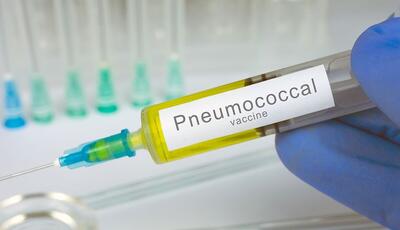

این واکسن عفونتهای خون و مغز و ریه کودکان را کاهش میدهد

واکسن پنوموکوک میتواند عفونتهای خون، مغز، ریه و.. را در سطح کشور به میزان قابل توجهی کاهش دهد، طبق برنامه واکسیناسیون جدید ۳ دز آن در ۲، ۴ و ۱۲ ماهگی به نوزادان تزریق میشود.